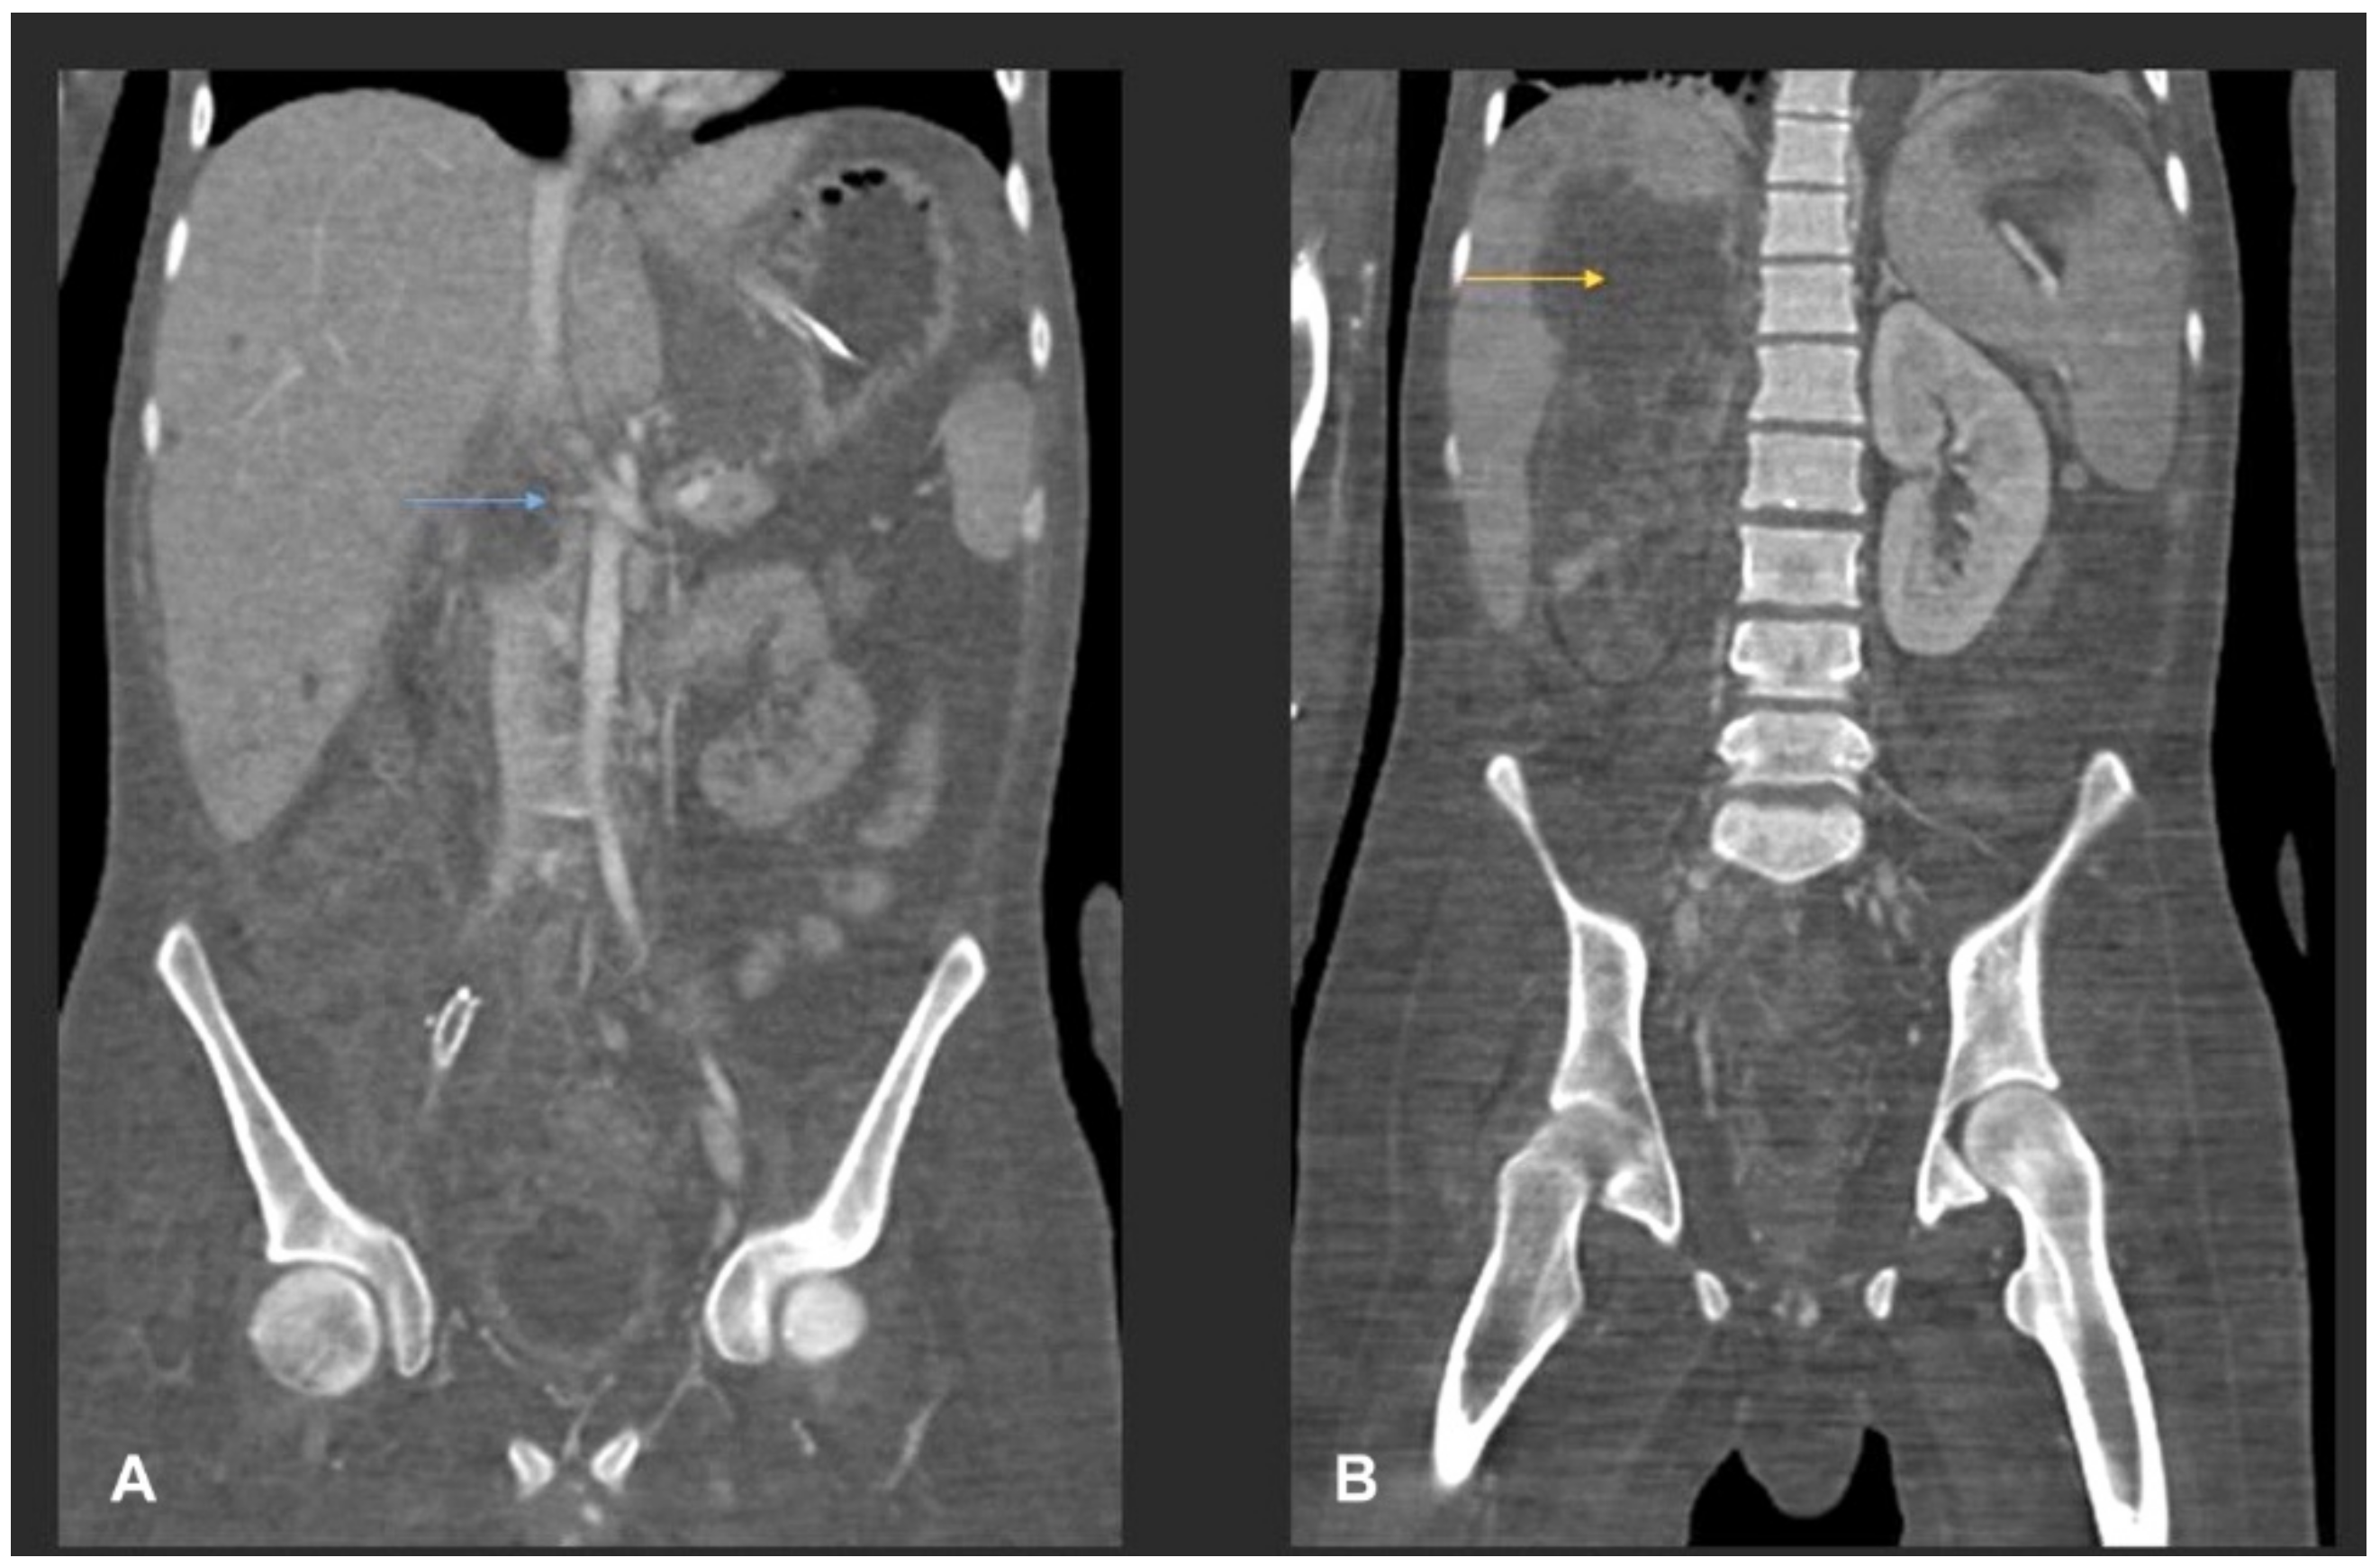

- Flicek, K.T.; Vikram, H.R.; De Petris, G.D.; Johnson, C.D. Abdominal imaging findings in gastrointestinal basidiobolomycosis. Abdom. Imaging 2015, 40, 246–250. [Google Scholar] [CrossRef]